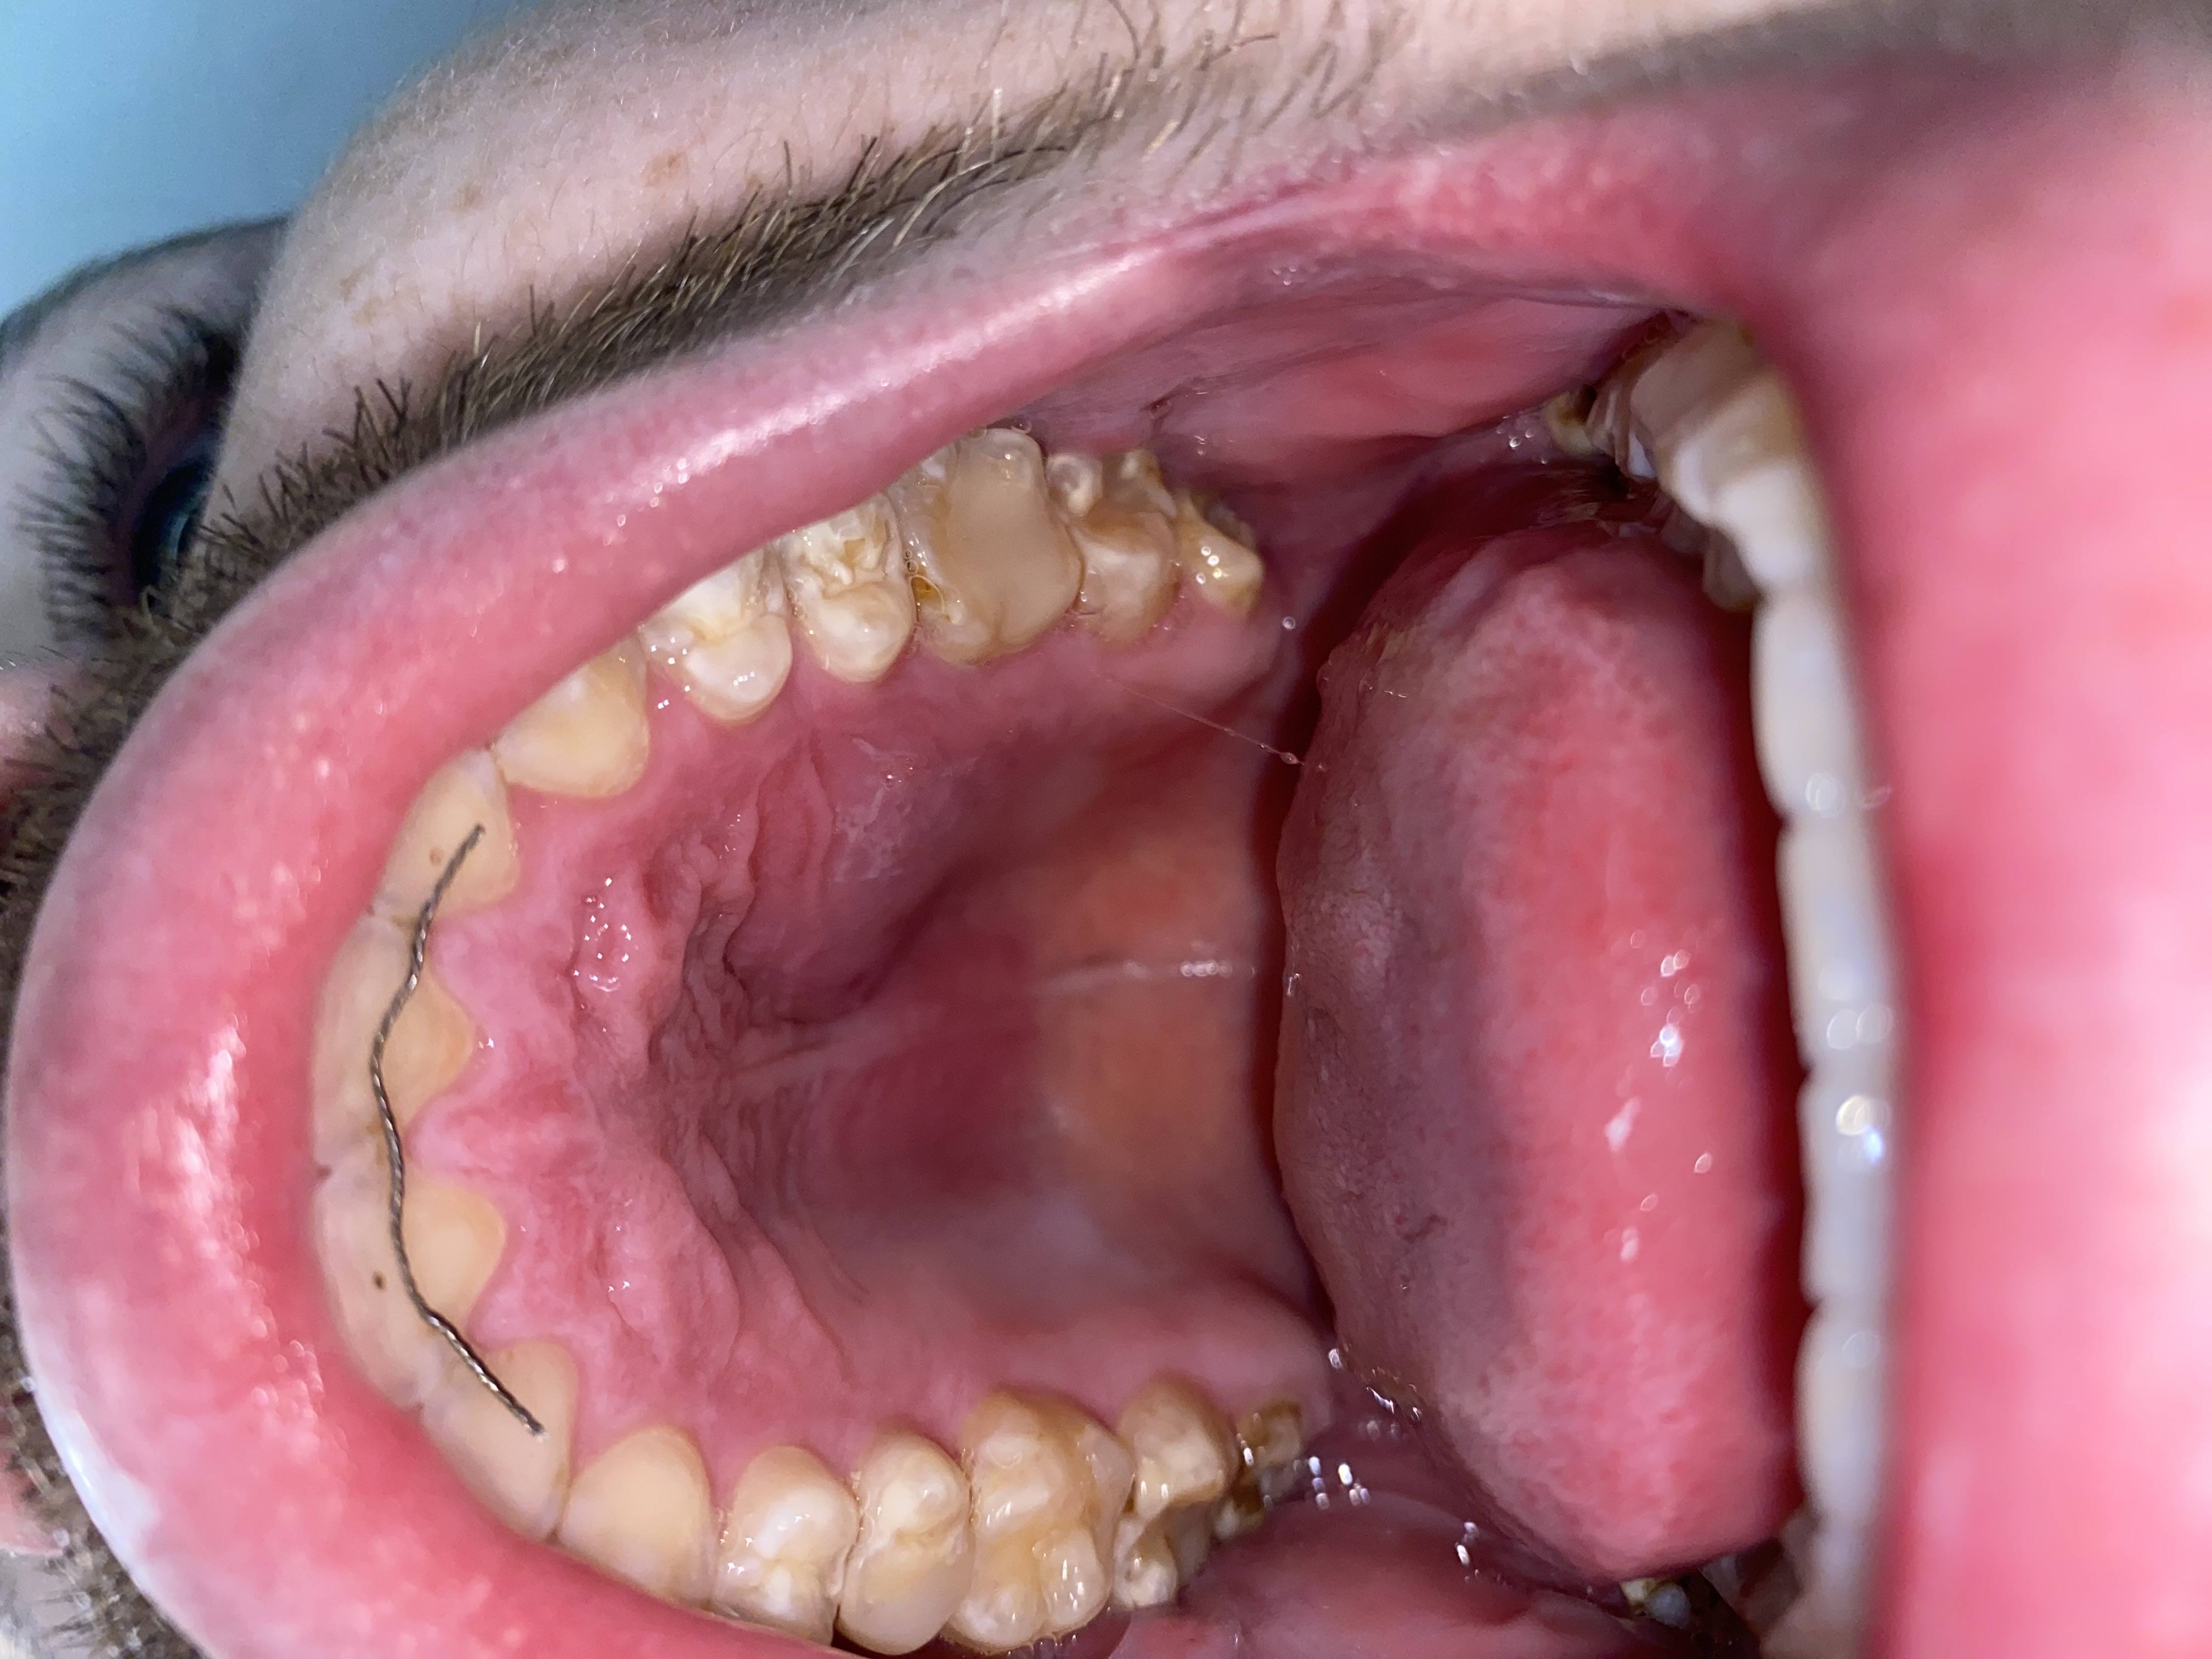

Ik heb een zwelling in mijn mond (gehemelte), maar deze doet niet pijn. Als ik er op druk komt er pus+bloed uit en zit bij mijn bovenste speekselklier. Misschien goed om te weten is dat ik een half jaar geleden daar ook een wortelkanaalbehandeling heb gehad. Kan iemand mij vertellen wat dit is? Ga vrijdag naar de tandarts maar heb grote angst dus wil graag van te voren al enig idee hebben wat ik kan verwachten.

Ik heb online vergelijkbare foto's gevonden vanuit academische bronnen. Daarin werd vermeld dat het een ontsteking/infectie kon zijn van de speekselklier. Is dit ook mogelijk? En zo ja wat zo voor beide een mogelijke oplossing zijn dat de tandarts zal doen?